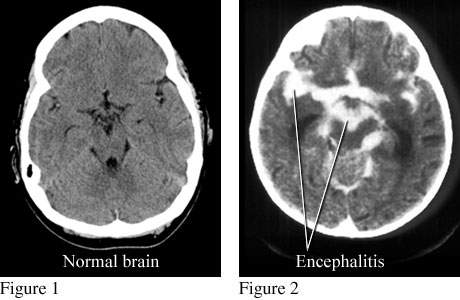

Encephalitis